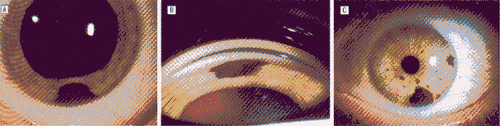

IPE腺瘤的鉴别诊断需包括几种情况(图2)。也许IPE腺瘤最重要的方面在于与虹膜和睫状体黑色素瘤、痣、特别是与痣的变型黑色素细胞瘤相鉴别。IPE腺瘤起源于虹膜后色素上皮层,并倾向于使虹膜基质移位。相比之下,虹膜痣和黑色素瘤起源于虹膜基质并与基质融合(图2,A,B)。IPE肿瘤通常呈深灰到黑色,而大多数黑色素瘤是棕色,色素相对较少,并且常常是浅色或无黑色素的。IPE腺瘤很少显露明显的血管,而黑色素瘤更可能有滋养血管和肿瘤的血管分布。IPE腺瘤通常有陡峭隆起的边界,而虹膜黑色素瘤常有清晰地位于虹膜基质内逐渐变坦的边界。

图2 相似于虹膜色素上皮(IPE)腺瘤的病损。A,典型的下方虹膜痣。B,图A病灶的房角镜检查所见。病灶融入虹膜基质,相似于虹膜黑色素瘤。C,虹膜黑色素细胞瘤。临近基质可见卫星灶。D,图C病灶的近景。病灶有粗糙、皱折的表面并且在角膜后表面病灶受压可见。诊断由组织病理学检查确实。E,IPE中间带囊肿。扩瞳后病灶呈现典型的延伸或梭样的形状。F,IPE中间带囊肿的超声活体显微镜检查,显示虹膜中间部分后方的卵形囊性团块。G,通过裂隙灯后映照法可见IPE周边囊肿。病损透光。而IPE腺瘤特征性阻挡光线。H,IPE周边囊肿超声活体显微镜检查。在虹膜睫状体沟内可见圆的囊性病灶